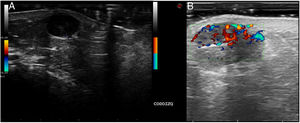

A 75-year-old woman diagnosed with a melanoma on the left arm in 2006 (Breslow thickness, 1.1 mm, treated with surgery and removal of lymph nodes) visited our department after 10 years due to a nodule measuring 1 cm on the left elbow, near the melanoma scar. Doppler ultrasound was performed using a MyLab™ 25 Gold device with PRF 740 and 79% gain, and revealed a rounded hypoechoic image with posterior enhancement and lateral shadows, with no flow in Doppler mode, compatible with a simple cyst. The imaging was repeated with the MyLab™ Class C device with PRF 750 and 80% gain, and revealed a hypoechoic image with abundant Doppler flow in the interior, compatible with melanoma metastasis. The lesion was excised, and melanoma metastasis was confirmed (Fig. 1).